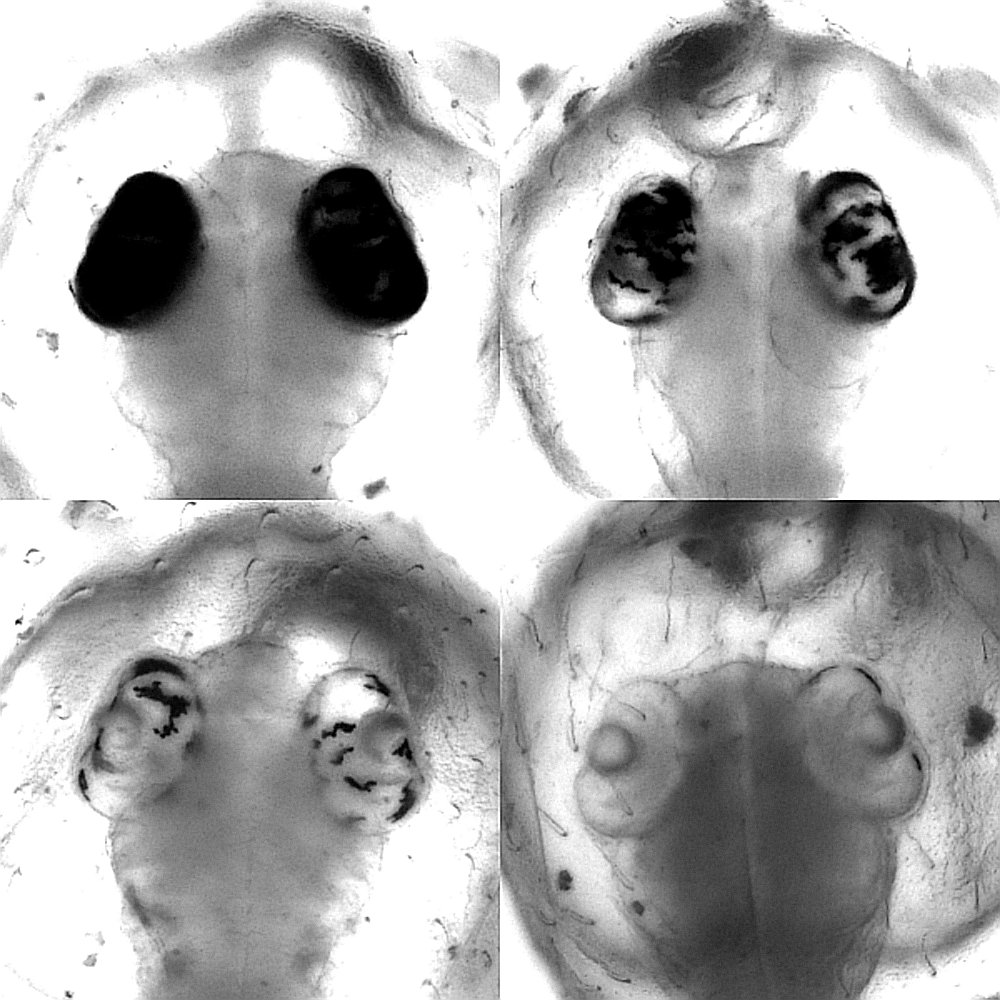

Dass Base-Editoren im lebenden Organismus mit großer Effizienz arbeiten und sich sogar für ein genetisches Screening eignen, haben die Heidelberger Wissenschaftler in einer weiteren Studie nachgewiesen. Im Versuch mit Japanischen Reiskärpflingen konnten sie zeigen, dass diese lokal begrenzten, gezielten Veränderungen einzelner DNA-Bausteine eine Wirkung entfalten, die sonst nur durch die vergleichsweise aufwändige Zucht von Organismen mit verändertem Erbgut erreicht wird. Das Forschungsteam am COS hat dabei in Zusammenarbeit mit Dr. Dr. Jakob Gierten, Kinderkardiologe am Universitätsklinikum Heidelberg, bestimmte Genmutationen in den Blick genommen. Diese Mutationen standen im Verdacht, angeborene Herzfehler beim Menschen auszulösen. Durch die Veränderung einzelner DNA-Bausteine der entsprechenden Gene im Modellorganismus konnten die Wissenschaftler Fischembryonen mit den beschriebenen Herzfehlern nachahmen und studieren. Der gezielte Eingriff führte bereits in den frühen Embryonalstadien der Fische zu sichtbaren Veränderungen am Herzen, wie Doktorandin Bettina Welz und Dr. Alex Cornean, zwei der Erstautoren der Studie aus dem Team von Prof. Wittbrodt, ausführen. Dadurch konnten die Forscherinnen und Forscher den ursprünglichen Verdacht bestätigen und einen ursächlichen Zusammenhang zwischen genetischer Veränderung und Krankheitsbild herstellen.

Ermöglicht wurde der präzise Eingriff in das Erbgut der Fischembryonen durch die eigens entwickelte, online verfügbare Software ACEofBASEs. Damit lassen sich Stellen in Genen identifizieren, die sehr effizient zu gewünschten Veränderungen an den Zielgenen und daraus resultierenden Proteinen führen. Der Japanische Reiskärpfling ist dabei, so die Wissenschaftler, ein exzellenter genetischer Modellorganismus, um Mutationen zu modellieren, wie sie bei dem jeweiligen Patienten auftreten. „Unsere Methode ermöglicht eine effiziente Screening-Analyse und könnte damit einen Startpunkt für die Entwicklung individualisierter medizinischer Behandlung bieten“, so Jakob Gierten.